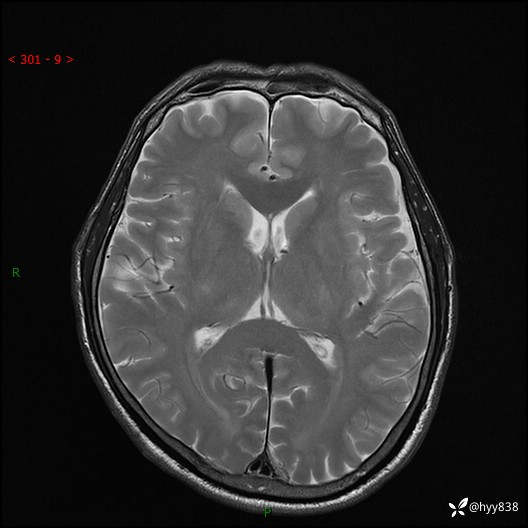

颅脑MRI平扫